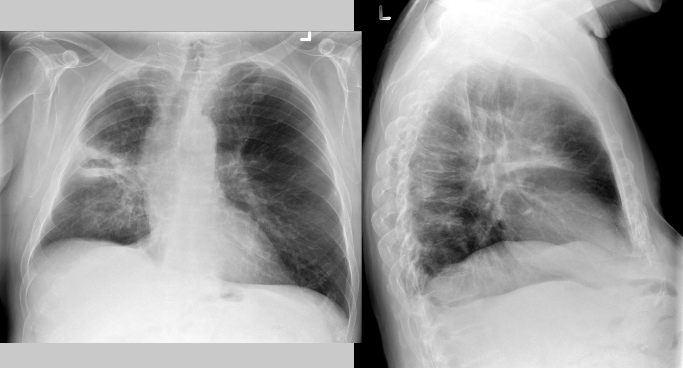

Describe the RA for alveolar pneumonia (this pic and pic in description)

homogenous consolidation in segments or the entire lung — air bronchograms are present (when an entire lobe fills with fluid but has not collapsed)

PT is 43 yr old male presenting with productive cough and fever/chills

What pathology is present?

pneumonia — alveolar/pneumococcal pattern